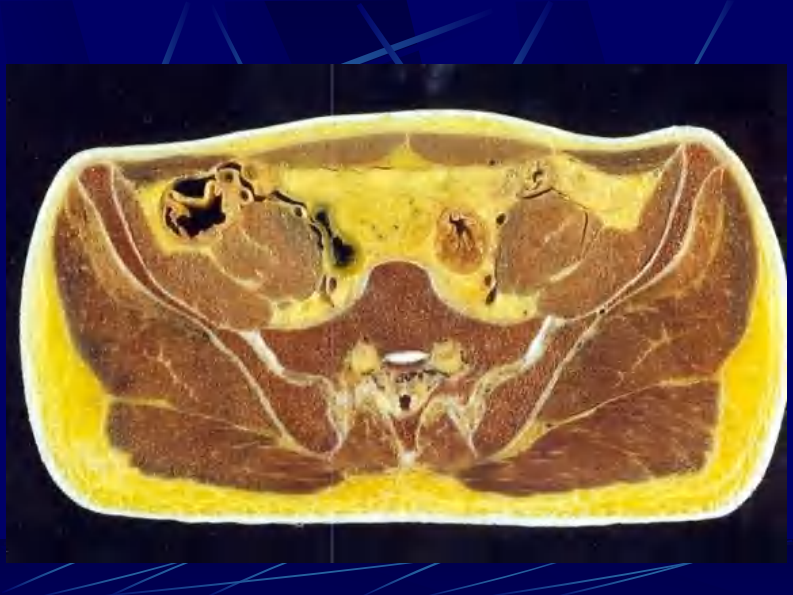

11 男性盆部和会阴断层解剖.pdf